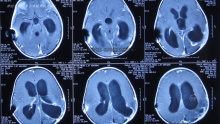

脑室双侧侧脑室加四脑室引流